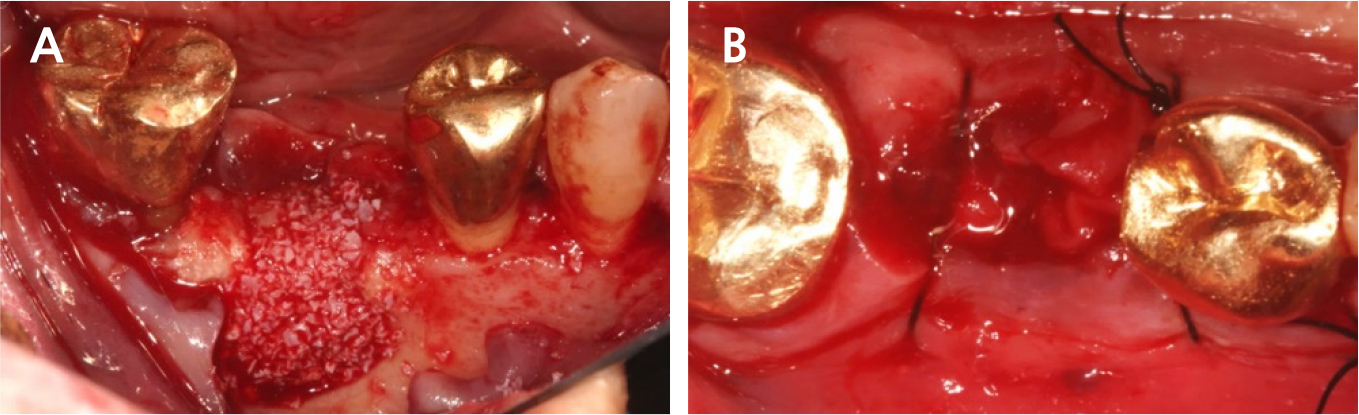

During implant removal, the buccal remnant marginal bone was brittle and easily fell off, and the large bone defect area needed additional treatment for delayed implant placement(Fig. 4). After augmentation with a combination of 0.25 g of deproteinized bovine bone mineral (DBBM) (Bio-Oss®; Geistlich, Wolhusen, Switzerland) and 250 mg of DBBM with 10% porcine collagen (Bio-Oss collagen®; Geistlich), double layer of native bilayer collagen membrane (Bio-Gide®; Geistlich, Switzerland) was applied. The socket was sutured in an open healing state using hidden X suture (Figs. 5 and 6).9

There was slightly sloughing tissue in the open healing area one month later, the healing of the socket seemed like a crater pattern. However, after 4 months, high-quality keratinized mucosa was secured (Figs. 7, 8, and 9). At the time of flap opening for implant placement, the bone was maintained at the ideal height and width. The bone quality was sufficient to get initial stability (Fig. 10).